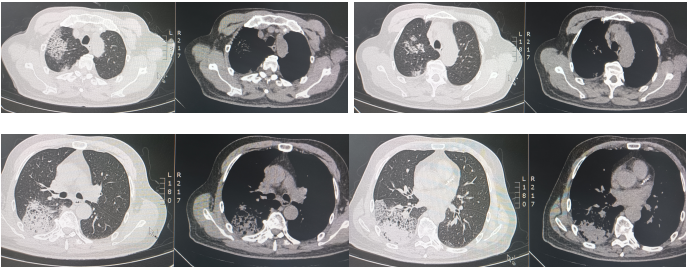

入院后给予奈诺沙星0.5 g qd ivgtt、头孢他啶阿维巴坦2.5 g q8h ivgtt经验性抗感染治疗。治疗5天后复查相关指标:白细胞计数9.69×109/L,中性粒细胞绝对数7.31×109/L,C反应蛋白90.4 mg/ml,血清淀粉样蛋白>288.00 mg/L,红细胞沉降率测定94 mm/h;胸部CT:右肺上叶、下叶间质性炎症,左下肺小结节,炎性结节可能(图2)。提示病变无明显好转,告知家属病情后再次行气管镜检查,行病原学检查及病理检查,结果示:BALF涂片、培养、GM均阴性;BALF NGS回报:流感嗜血杆菌、烟曲霉。冷冻肺活检病理:(右肺下叶后基底段)肺组织急、慢性炎,肺泡腔内见纤维素样渗出物伴泡沫细胞聚集。免疫组化结果:CK7(+),TTF1(+),SMA(平滑肌+),NapsinA(+),PGM-1(+),Ki-67(+, 5%),P40(+),CD68(+)。考虑真菌感染不除外于8月31日加用伏立康唑0.2 g q12h ivgtt;醋酸卡泊芬净70 mg qd ivgtt抗真菌对症治疗。图2 2024年8月27日复查胸部CT较8月21日胸部CT无明显吸收9月5日再次复查相关指标:白细胞计数12.38×109/L,中性粒细胞绝对数9.27×109/L,C反应蛋白151.46 mg/ml,血清淀粉样蛋白>288.00 mg/L,红细胞沉降率117 mm/h。胸部CT:右肺散在间质性炎症,左下肺新发炎症灶,较前进展,左下肺小结节,范围较前增大(图3)。图3 2024年9月5日胸部CT右下肺炎症较8月27日进展,左肺出现新发炎症灶9月5日行MDT讨论,考虑感染继发机化性肺炎不除外,建议在目前抗感染治疗保驾下予中等剂量激素治疗,并严密动态观察相关指标。9月6日起治疗上加用甲泼尼龙琥珀酸钠80 mg qd ivgtt。治疗1周后(9月12日)复查相关指标:复查炎症标志物:白细胞计数16.47×109/L,中性粒细胞绝对数14.79×109/L,C反应蛋白11.08 mg/ml,血清淀粉样蛋白25.388 mg/L,红细胞沉降率28 mm/h。胸部CT:双肺散在间质性炎症(右肺为著),较前吸收(图4)。9月12日调整激素剂量为醋酸泼尼松片35 mg qd口服;9月19日患者无发热,无明显咳嗽、咳痰不适,予出院并嘱出院后维持醋酸泼尼松片35 mg qd口服,1周后每周减5 mg,减至20 mg后维持1周并复查胸部CT,根据胸部CT结果调整剂量。10月21日患者门诊复查胸部(图5),较前明显吸收,激素调整为醋酸泼尼松片10 mg qd,目前在持续随访中。治疗期间感染相关指标变化情况如图6所示。机化性肺炎(organizing pneumonia,OP)是一种肺组织修复过程,是以肺泡腔/管内有息肉状肉芽组织为病理特点,主要由成纤维细胞、肌成纤维细胞和疏松结缔组织基质构成[1]。同时与其他肺损害,如血管炎、淋巴瘤、肺癌、过敏性肺炎(hypersensitivity pneumonitis,HP)、嗜酸性粒细胞性肺炎(eosinophilic pneumonia,EP)、急性间质性肺炎(acute interstitial pneumonia,AIP)、非特异性间质性肺炎(nonspecific interstitial pneumonia,NSIP)或普通型间质性肺炎(usual interstitial pneumonia,UIP)关系密切。OP具有复杂的多态性,具有急性、亚急性和慢性多种形式。OP可以根据病因分为隐源性机化性肺炎(cryptogenic organizing pneumonia,COP)和继发性机化性肺炎(secondary organizing pneumonia,SOP)。COP与SOP在临床表现、影像表现和肺功能无明显差异[2],当有相关病因时诊断为SOP,当临床未发现相关潜在疾病时诊断为COP。OP的概念最早在肺炎链球菌的大叶性肺炎中被阐述,OP的发病机制目前主要认为肺泡上皮损伤,纤维蛋白渗出,导致成纤维细胞增生-肌成纤维细胞增生[3]。机化存在于多种肺损伤中,具有相同的本质,无论是局灶性还是弥漫性肺损伤,以成纤维细胞增殖为特征的机化是一种常见且几乎普遍的反应[4],机化被认为是对炎症渗出的反应和局限,很可能代表疾病的一个阶段,而不是独立的疾病。所以如果有确认感染的证据,虽然CT上发现有机化的特征,临床诊断OP往往是不必要的,除非这种机化是主要表现,而且改变了疾病进程。因此关注整体,将OP作为疾病的一个阶段,有利于建立对疾病的全息认识。OP没有特异的临床特征,患者可能出现发热、咳嗽、乏力、轻度呼吸困难、厌食症和体重减轻等,类似于流感[5],临床表现不特异。有些患者接受经验性抗生素治疗后往往无效,且疾病可能会迅速进展,导致严重的呼吸困难,甚至是ARDS,往往存在延误诊断。有文献报道大部分OP患者为不吸烟患者,肺功能主要表现为限制性通气障碍,也可表现为混合型和阻塞性通气障碍[6]。也有学者研究SOP患者有胸腔积液,而COP患者未报告胸腔积液[7]。因此,胸腔积液似乎与背景疾病有关,而与OP本身无关。OP的CT表现可以按照发生率分为典型和非典型模式[6],多数患者表现为典型模式,即多灶性实变,常被描述为斑片状肺泡阴影,一般位于下肺外周或支气管血管周围;实变可伴有支气管充气征,并可伴有散在的磨玻璃病变或小结节。而非典型的病变表现多样,可为磨玻璃影,也可为结节或肿块样表现、反晕征、铺路石征、小叶周围病变、线性和带状阴影以及网状结构。OP虽然有多种影像学表现,但均不特异,类似的表现同样可以出现在其他疾病中。例如,迁移性病灶可提示嗜酸性粒细胞性肺炎、感染、血管炎和复发性出血[8];弥漫性微小结节可见于过敏性肺炎、细支气管感染和炎症;反晕征可见于多种感染、非感染性肉芽肿异常,甚至原位腺癌[9]。因此诊断OP不能单纯依靠CT,需要结合临床和病理特征。目前针对OP的治疗,COP主要是以糖皮质激素为主[10],SOP需要兼顾原发疾病治疗及激素应用,因此我们需要尽早明确病理,及时治疗,减少不良预后。针对重症患者,尽早获取病理是必要的。此病例我们初步诊断为CAP,予抗感染治疗后疾病进展,及时行二次支气管镜冷冻肺活检+灌洗,同时通过mNGS及病理检查,最终被诊断为SOP,经激素抗炎治疗后症状好转,影像学提示病灶明显吸收。总之,OP在临床上并不少见,但由于其临床表现无特异性且CT表现多样,所以及时正确诊断OP罕见,诊断OP需要结合临床和病理特征,只有当OP成为主导性特征且干扰了疾病进程,才被冠以OP的诊断。针对初诊为肺炎的患者,当经验性抗感染治疗效果欠佳时,需要及时明确病原学检查及病理诊断,及时修改诊断及治疗路径,及时干预[11]。[1] CottinV,CordierJF. Cryptogenic organizing pneumonia[J]. Semin Respir Crit Care Med, 2012, 33(5): 462-475.